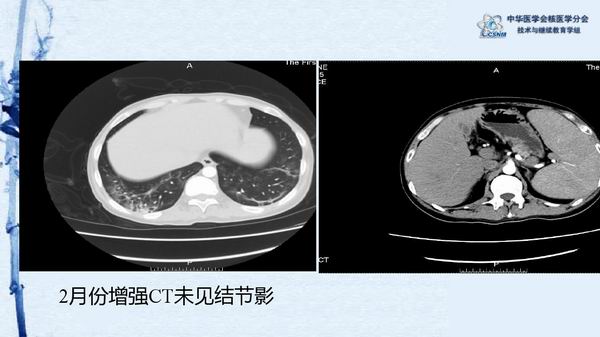

病例49:PET-CT显像诊断淋巴瘤相关噬血细胞综合征一例-【CSNM继教学组】程兵 郑州大学第一附属医院